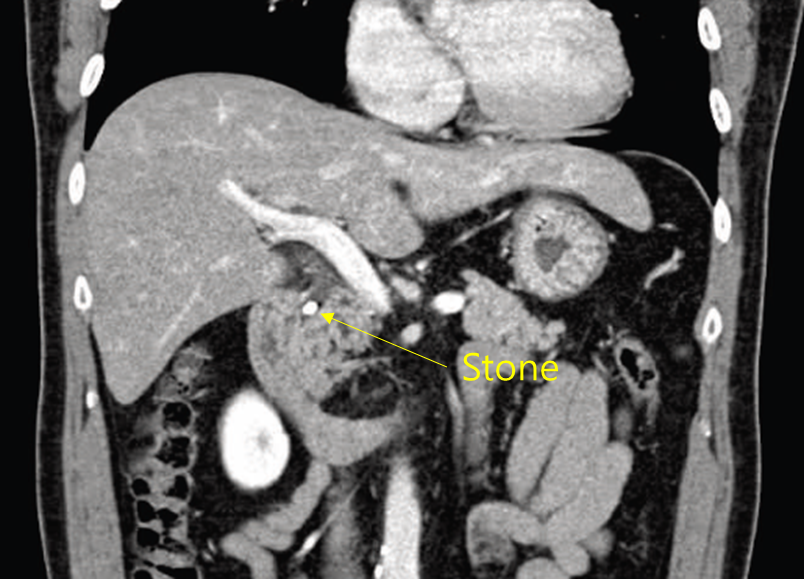

48세 남자가 5일 전부터 윗배가 아프고 열이 나서 응급실에 왔다. 평소 음주는 하지 않는다고 한다. 공막은 노랗고, 오른쪽 윗배에 압통이 있으나 반동압통은 없다. 혈압 123/95 mmHg, 맥박 100회/분, 호흡 20회/분, 체온 38.5℃ 이다. 혈액검사 결과는 다음과 같다. 복부 컴퓨터단층촬영 사진이다. 치료는?

Img | CT: CBD stone, causing upstream biliary dilatation |

CT상 CBD stone이 확인되며 Charcot’s triad가 확인되므로 acute cholangitis 진단 하, ERCP를 통한 CBD stone removal을 시행한다.

• Biliary obstruction의 원인 감별을 위해 CT 시행, radiopaque CBD stone이 확인되며 upstream biliary dilatation이 관찰된다.